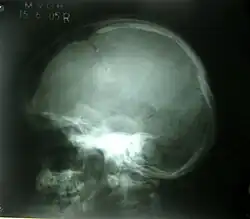

A common disease associated with the crown includes the cerebrospinal fluid leak, which involves the excess removal of fluid within the meninges. The cerebrospinal fluid leak is mainly caused by a head, brain, or spinal injury which tears the meninges membrane. The excessive leakage of the cerebrospinal fluid leads to symptoms that include intense headaches often localised to the crown.[13] An extreme sign of this disorder includes the leakage of fluid from the patient's ears and nose.[13] The diagnosis of the cerebrospinal fluid leak is determined from examinations including a computerised tomography scan which involves an X-ray image of parts of the skull including the crown.[14] Health professionals offer treatments to manage the symptoms associated with the disease. For example, consuming fluids such as water aims to stop excess leakage and reduce headaches, and antibiotics are also provided if signs of infection are clear such as fever and chills.[15]

Bone fractures to the crown of the head are linear or depressed and range in severity based on the impact to the skull. The linear fracture involves a break to the skull whereas the depressed fracture results in the scatter of skull fragments.[19] The skull fractures are mainly caused by incidents involving a vehicle, assault, or a fall. In more severe cases, penetrating skull fractures are caused by an object such as a metal rod or bullet breaking through the skull completely. Based on the severity of the fracture, symptoms may include nausea, memory loss, concussion, bruise, and lethargy. Another symptom such as bleeding results in the build-up of pressure in the skull since it is an enclosed cavity and thus pushes the brain to the brainstem opening leading to a coma.[20] Diagnosis occurs due to a range of physical exams which identifies the extent of the injury and possible treatments. For example, the computerised tomography scan identifies the site of the fracture and any associated injuries to the brain, whereas magnetic resonance imaging highlights the damaged tissue. The treatments of severe skull fractures include surgery and medication to avoid infection, however, for linear fractures treatment involves rest for approximately 5 to 10 days, so that the crown can heal.[21]

Gorham's disease is a condition that targets the human musculoskeletal system including the crown of the skull. The chronic disorder involves the progressive loss of bone, although, symptoms such as intense pain are not evident during the initial stages.[22] The cause of the Gorham disease has not been discovered, however, cells associated with the breakdown of fragile and old bones which include osteoclasts are considered to be the main link towards identifying the cause. The symptoms of the disease are clear after a fracture to the crown of the skull causing patients to experience abnormal deformities as well as issues to the nervous system.[23] Diagnosis occurs through physical exams such as X-rays and magnetic resonance imaging which find the decrease in bone mass (osteolysis) and deformities. Treatment of the disease involves a range of techniques to prevent spread from the skull to the spine or chest of the patient. Chemotherapy and surgery, as well as lifestyle changes such as consuming a diet of high protein, aim to minimise the severity of the disease.[24]